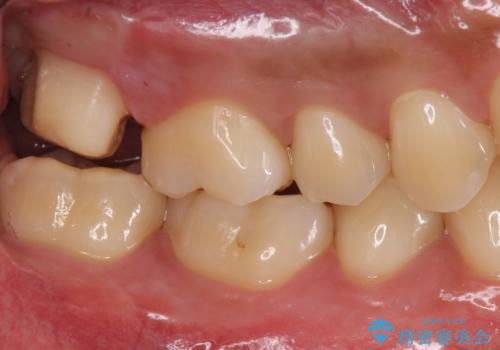

- 銀歯を白くしたいとのことで来院されました。

歯を覆っている銀の詰め物の面積が広く、セラミックで同じ形態にすると強度に不安が残るため被せ物での修復処置を行っていきます。

ブラッシングが上手な患者様であったため歯茎の締りもよく、大変適合の良い被せ物を装着することができました。